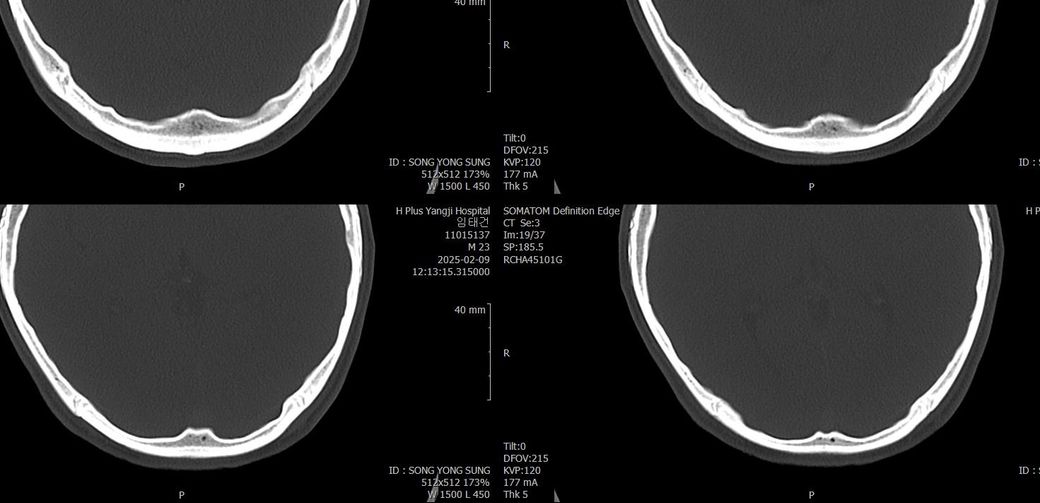

두개골 수술 또는 골절 의심되는 상황인데 엑스레이와 ct사진을 한번 봐주실 수 있나요?

2~3일 정도 기억이 없었는데 그때 머리를 다쳤는지 바로 x-ray와 ct를 찍어봤는데 한번 봐주실 수 있을까요? 진단 목적이 아닌 확인 목적입니다

빨갛게 동그라미 친 곳은 금속물질이 의심도는 부근입니다

• 4번 째 사진